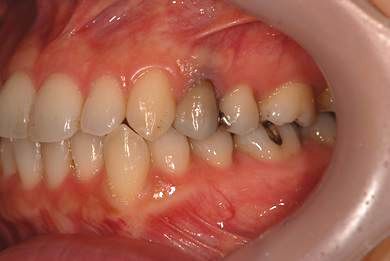

| 性別/年齢 | 女性 / 34歳 | ||||||||||||||||||||||||||||||||

| 主訴 | 以前虫歯を治療して金属を入れたところが、再び虫歯になったのか、軽くしみたり違和感がある。 | ||||||||||||||||||||||||||||||||

| 治療方針 | セラミック治療にて、審美的回復を行う。 | ||||||||||||||||||||||||||||||||

| 治療内容 | メタルボンドセラミッククラウン1本(メタルボンド用土台1本) | ||||||||||||||||||||||||||||||||

| 総治療費 | 125,685円 | ||||||||||||||||||||||||||||||||

| 治療期間 | 3ヶ月 |